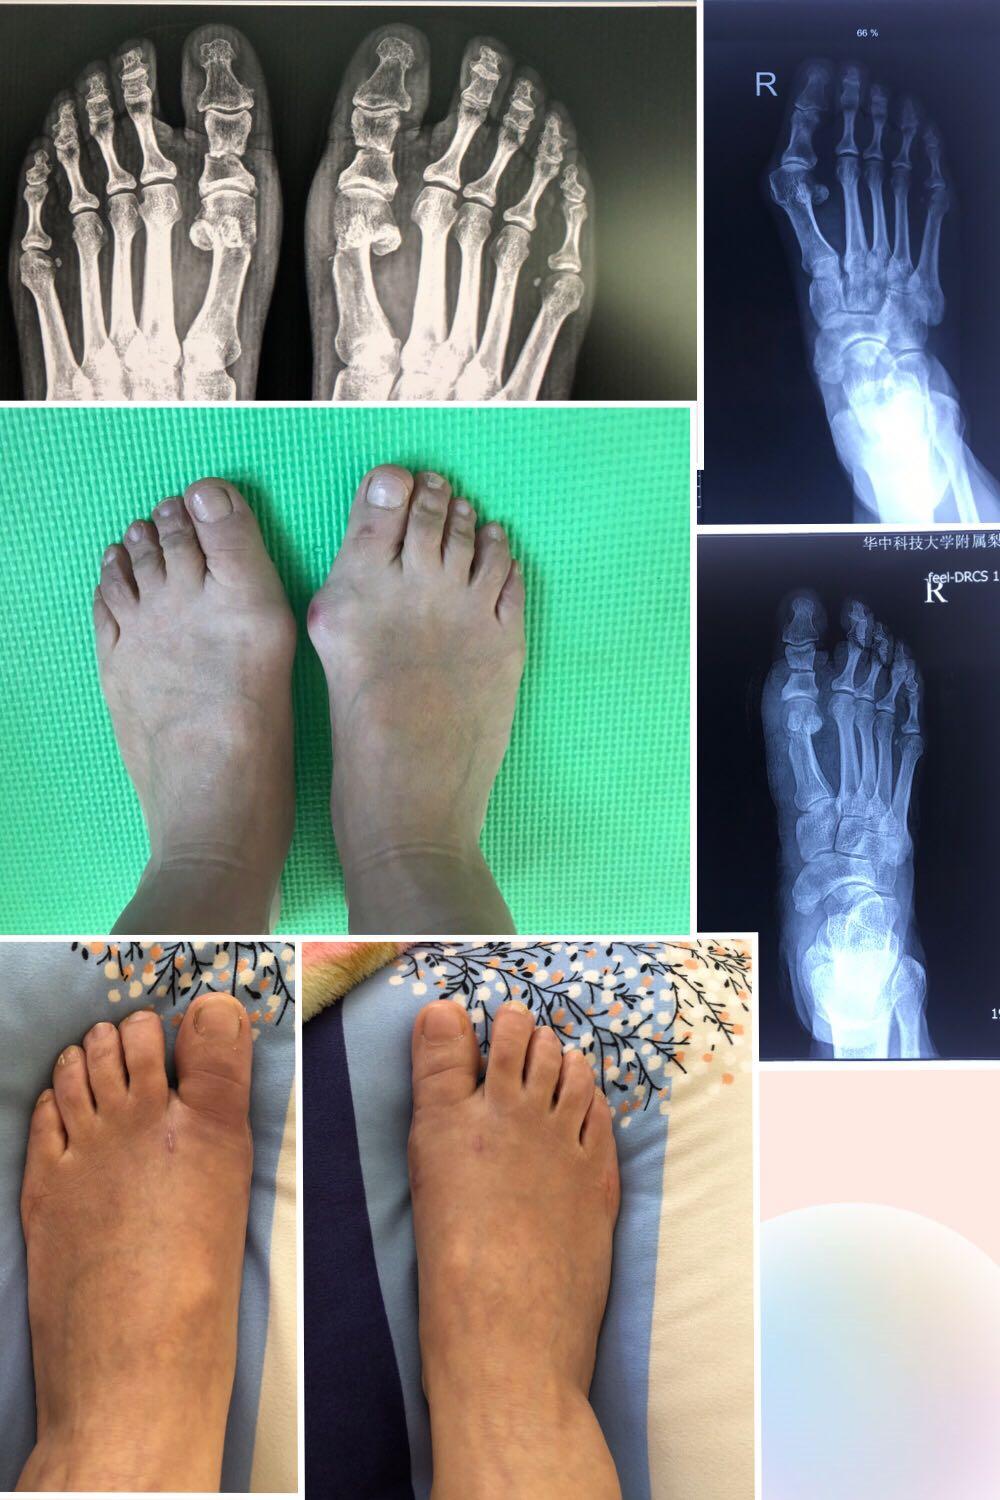

前后对比

手术方式:双侧Chervon + Akin截骨术(可吸收螺钉固定),拇囊松解+拇内收肌离断术

手术马上半年了,最大的改善是踝关节不再疼痛了,走路八字脚明显改善。当然,穿鞋方便多了。亚洲人的胖胖脚 还是很明显的,脚现在缩窄了一厘米左右。

下面是9.17好给一位同行做的手术,18号拍片,换药的情况,大家都很满意,接下来就是期待长期效果的满意了。